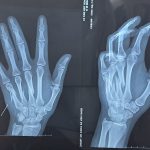

ĐIỀU TRỊ THÀNH CÔNG CA “GÃY XƯƠNG BÀN TAY” CHO BỆNH NHÂN 21 TUỔI

(benhvienhatrung.vn) – Vừa qua, Bệnh viện Đa khoa Hà Trung điều trị thành công “gãy xương bàn tay” bằng phương pháp kết hợp xương...